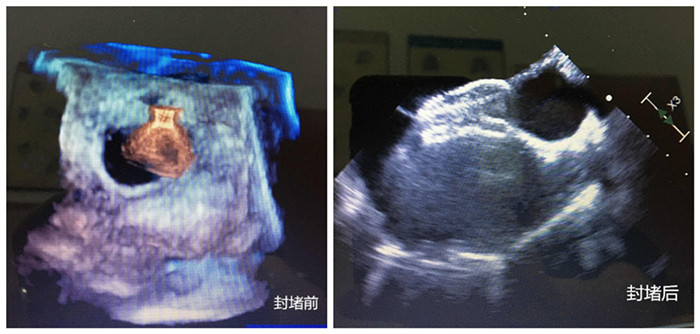

無(wú)影燈下,主刀醫(yī)生周珉在小強(qiáng)的右腋下切了一個(gè)長(zhǎng)度為4cm左右的切口,隨后,在經(jīng)食管探頭的引導(dǎo)下,封堵器順利通過(guò)心臟缺損部位,完成釋放和固定,牢牢地堵住缺口,“心臟正常的血液循環(huán)途徑恢復(fù)!”僅30分鐘,小強(qiáng)的心臟修補(bǔ)成功。

封堵前、封堵后兩張圖

守在手術(shù)室外的家人表示難以置信。三天后,小強(qiáng)便順利出院。